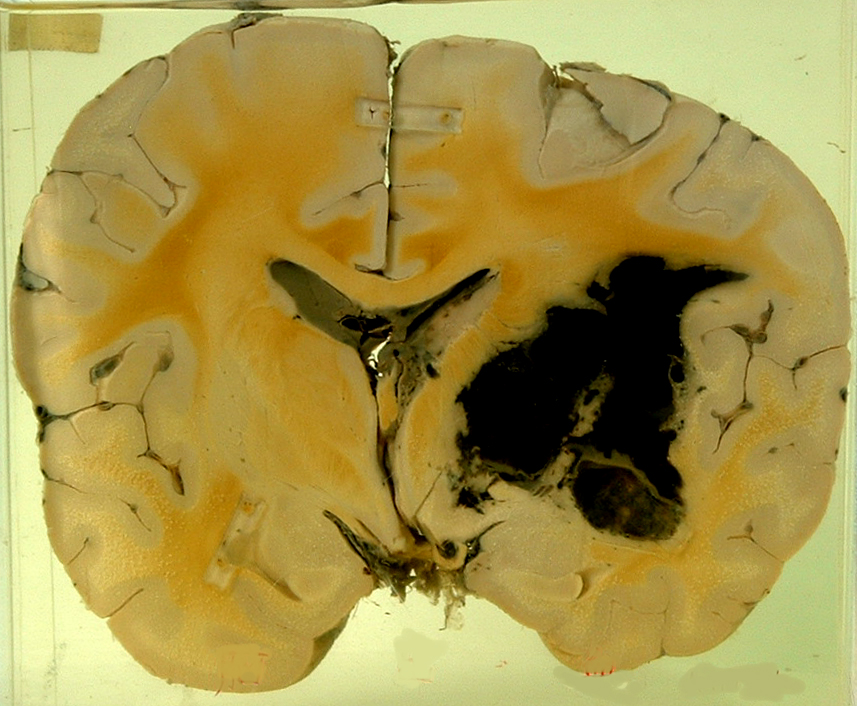

3.Hemorrhage of the brain